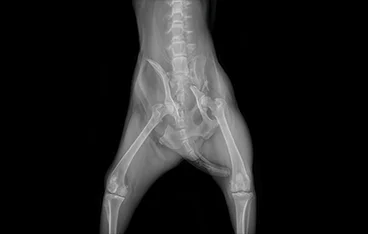

• 골반골절

• 골반골절 수술 전

골반골절 수술 후